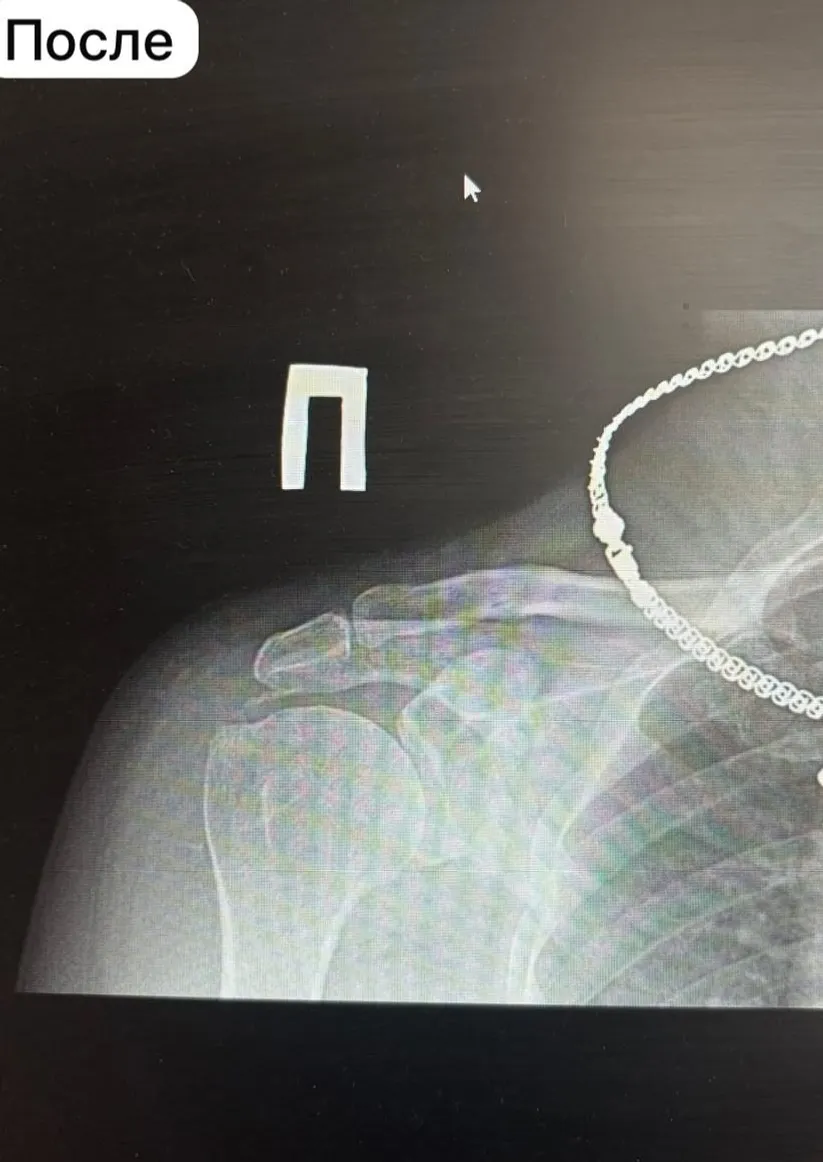

В городской клинической больнице №1 Стерлитамака впервые врачи инновационным методом удалили пациенту отложения кальцината плечевого сустава. Процедура называется барбатаж, пояснил главврач Ильшат Яппаров.

Врачи отделения травматологии и ортопедии через небольшие игольчатые проколы, без единого надреза, удалили кальциевые отложения объемом 2 см³. Тем самым избавили мужчину от болей и увеличили подвижность суставов.